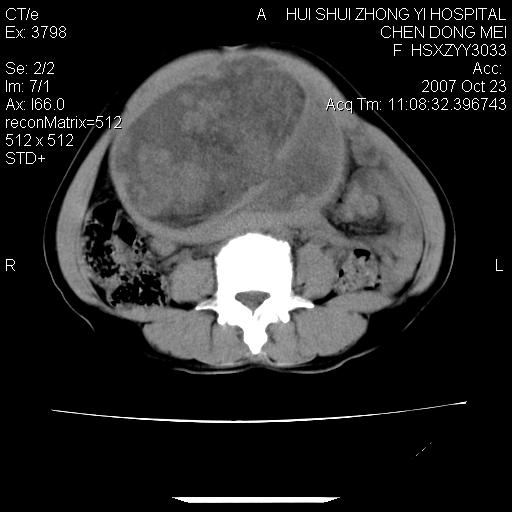

标题: CT10156:女.43岁,发现中下腹部包都块2年

发现中下腹部包都块2年。2年来月经不规律。

腹腔巨大软组织密度影,边缘光滑,包膜完整,内囊变坏死。腹膜后及盆腔内淋巴结肿大。结合病史考虑卵巢癌可能性大。

病变巨大,呈囊实性改变,包膜较厚且完整,内见分膈,周围脏器明显受压移位,病变与左侧附件关系密切,考虑来源左侧附件的囊腺瘤,不除外癌变可能;畸胎瘤可能性较小。

病变巨大,呈囊实性改变,包膜较厚且完整,内见分膈,周围脏器明显受压移位,病变与左侧附件关系密切,考虑来源左侧附件的囊腺瘤,盆腔内见肿大淋巴结,不除外癌变可能。

病变巨大,呈囊实性改变,包膜较厚且完整,内见分膈,周围脏器明显受压移位,病变与左侧附件关系密切,考虑来源左侧附件的囊腺瘤,不除外癌变可能